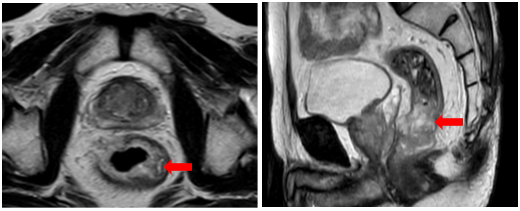

-         Cộng hưởng từ vùng tiểu khung (06/2025): Hình ảnh u trực tràng thấp, trực tràng cao T3N2Mx, MRF, EMVI (+)

+ Đoạn trực tràng thấp cách rìa hậu môn 24mm có tổn thương sùi loét vào lòng chiếm >3/4 chu vi, trên đoạn dài 47mm, sau tiêm ngấm thuốc mạnh, xâm lấn mạc quanh trực tràng, xâm lấn mạch máu, lân cận có vài hạch (>4 hạch) đường kính trục ngắn <5mm, ngấm thuốc sau tiêm

+ Đoạn cao cách rìa hậu môn khoảng 13cm, dày thành trên đoạn dài khoảng 44mm, chỗ dày nhất 11mm, thành ngấm thuốc mạnh, hạn chế khuếch tán, xâm lấn mạc quanh trực tràng, xâm lấn mạch máu, lân cận có vài hạch lớn nhất kích thước 9x9mm, ngấm thuốc sau tiêm

Hình 2: Đoạn trực tràng thấp cách rìa hậu môn 24mm có tổn thương sùi loét vào lòng chiếm >3/4 chu vi. Đoạn cao cách rìa hậu môn khoảng 13cm, dày thành trên đoạn dài khoảng 44mm, chỗ dày nhất 11mm